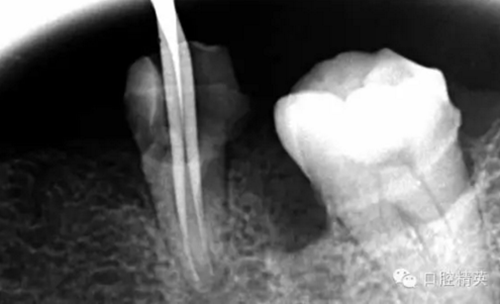

這個(gè)也是我目前接到最有難度的器械分離病例,從片子上看近中器械分離兩節(jié),曾在外院做過干尸,有七年。當(dāng)看到這個(gè)病例時(shí)我沒有多大的把握,因?yàn)槲沂巧硖幓鶎?,無顯微,無放大。我只有抱著試一試的態(tài)度,但是她是我們?cè)簝?nèi)員工,壓力很大。

現(xiàn)在開始看第二張片子我疏通的遠(yuǎn)舌根,有點(diǎn)問題哦!~

7.png

根尖孔偏移,或者是片子角度問題,導(dǎo)致我們很難判斷,感覺像是測(cè)穿。但是我們有根測(cè)儀(前提它是好的),因?yàn)楦鶞y(cè)儀是我們目前對(duì)根管測(cè)量最具有說服力,也是最為客觀事實(shí)的。根測(cè)儀沒有顯示一探入根尖下三分之一顯示“over”的情況(我用的是登士博根測(cè)儀)根管內(nèi)無滲出,可以測(cè)出根管的長度。那就證明工作長度的存在,和可信。在看看正題的近中根的器械,我想問問大家覺得是什么器械??

近中舌根疏通,兩根分離的器械都在近中舌根。花費(fèi)2個(gè)多小時(shí)。將它疏通下去還是離不開較長的時(shí)間,也就是耐心,它真的很重要哦!~第二個(gè)我覺得器械分離的疏通,就是在于能否建立旁路,那么怎么去建立這條路。我個(gè)人覺得首先挫的選擇,是k挫,是c+,還是別的什么。我的首選是8號(hào)c+,因?yàn)樗鼔蛴玻?號(hào)的k挫太軟,沒有辦法擴(kuò)下去,很容易碰到根內(nèi)部器械導(dǎo)致器械報(bào)廢,尖端變光亮。但是c+挫也不是那么完美,我擴(kuò)的時(shí)候用了4根8號(hào)新的c+挫,全部報(bào)廢。尖端彎曲90度的,有變成麻花的。這些都在提醒我可能用力過大,或者根管內(nèi)部太過于復(fù)雜。疏通時(shí)只有慢慢來,一點(diǎn)點(diǎn)的下千萬不要妄想一步到位。手法還是要輕柔否則你的器械一樣也會(huì)分離進(jìn)去。疏通到挎自己的器械的時(shí)候也是碰到分離的器械時(shí),這個(gè)時(shí)候最好是上下提拉,切勿旋轉(zhuǎn)向下,你只有盡量將該部位擴(kuò)開,為下一步往下疏通留有足夠的空間就好。而不是繼續(xù)向下旋轉(zhuǎn),這樣會(huì)導(dǎo)致器械的分離,加大你疏通的難度。